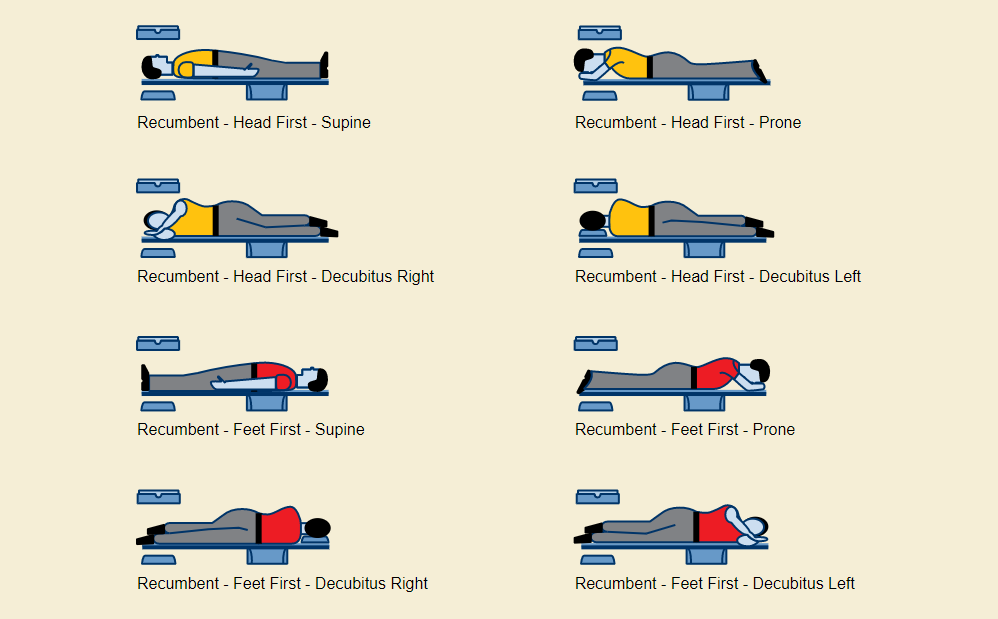

Patient Orientation Registry in System

- Set the orientation patient in system : Feet First – Prone

- This is to follow the orientation of wrist (base on anatomical position)

- Position the patient in head first prone position.

- Raise the patient’s arm above head in pronation position.